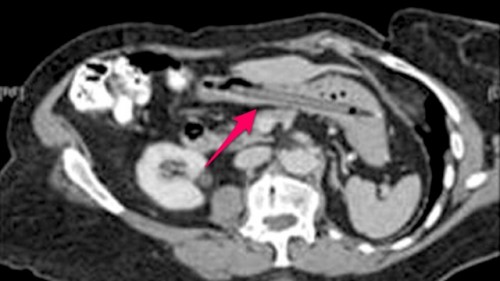

It's a story you hear every day- woman goes in to see her doctor due to rapid weight loss, and an x ray reveals that she's had a felt tip pen stuck in her stomach for the last 25 years. Here's more: On subsequent que...